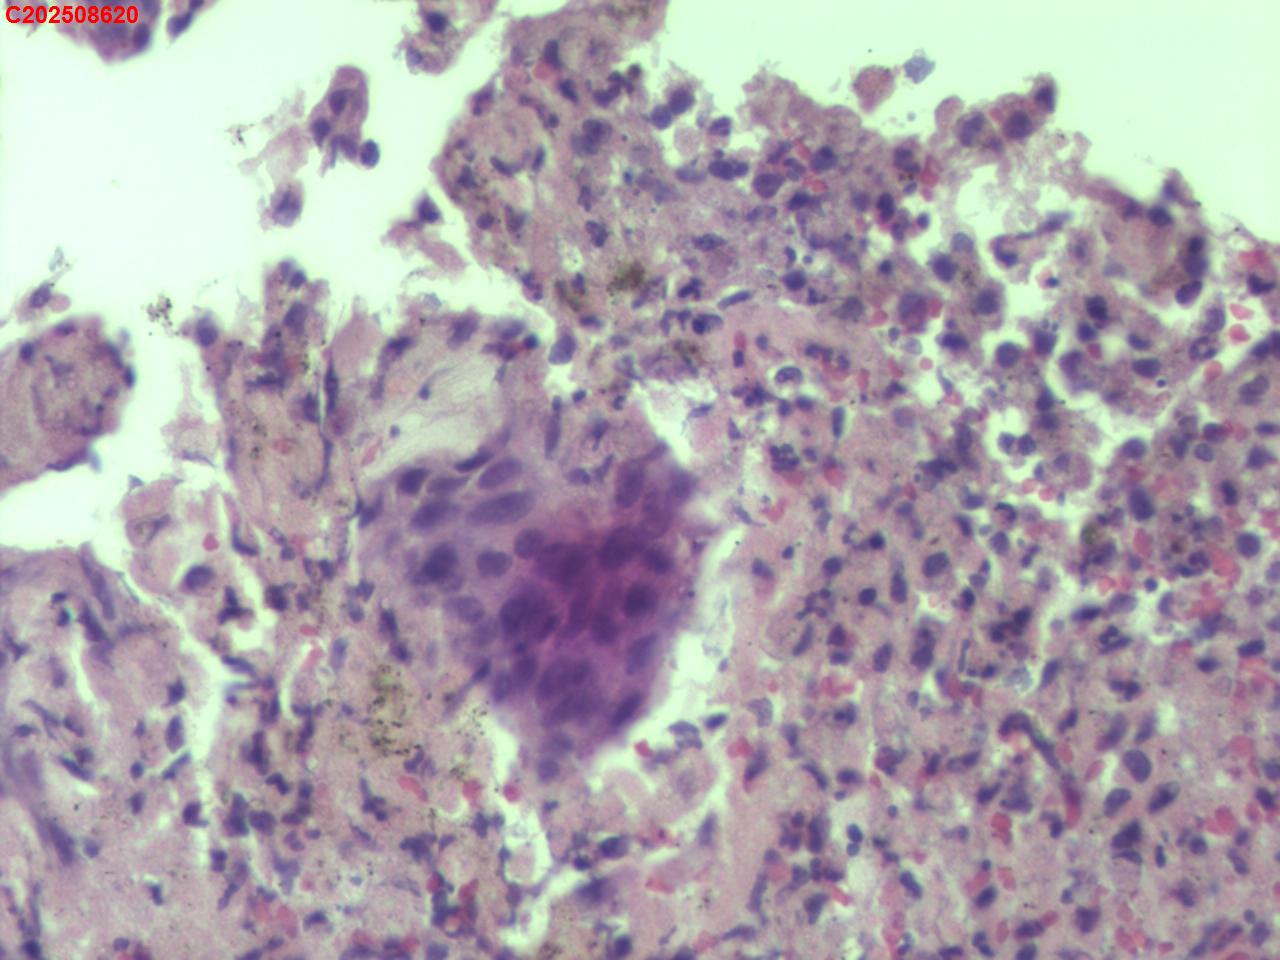

CT示:考虑右肺上叶炎症伴肺实变,右肺上叶前段支气管显示不明确,建议治疗后复查或支气管镜检查。纵膈多发淋巴结增大。右侧胸腔积液。主动脉及冠状动脉钙化。食道裂孔疝。

气管镜检查示:右肺上叶前段支气管开口可见脓苔附着,支气管开口狭窄,内可见灰黑色新生物阻塞右肺上叶前段支气管管腔。

者缘于10余天前无明显诱因出现发热,体温最高39.5℃,咳嗽、咳少量白痰,活动后气短,无盗汗,无咯血,无胸痛,无鼻塞、流涕,无恶心、呕吐,无腹痛、腹泻。就诊廊坊市第四人民医院,查胸部CT示:考虑右肺上叶炎症伴肺实变,右肺上叶前段支气管显示不明确,建议治疗后复查或支气管镜检查。纵膈多发淋巴结增大。右侧胸腔积液。主动脉及冠状动脉钙化。食道裂孔疝。结核感染T细胞检测阳性。气管镜检查示:左侧主支气管、上叶、下叶及各段支气管未见异常。右侧主支气管未见异常。右侧中间段支气管可见碳沫沉积。右肺上叶前段支气管开口可见脓苔附着,支气管开口狭窄,内可见灰黑色新生物阻塞右肺上叶前段支气管管腔。肺泡灌洗液查结核分枝杆菌复合群阳性。

有坏死,有上皮样细胞,做个抗酸染色看看。